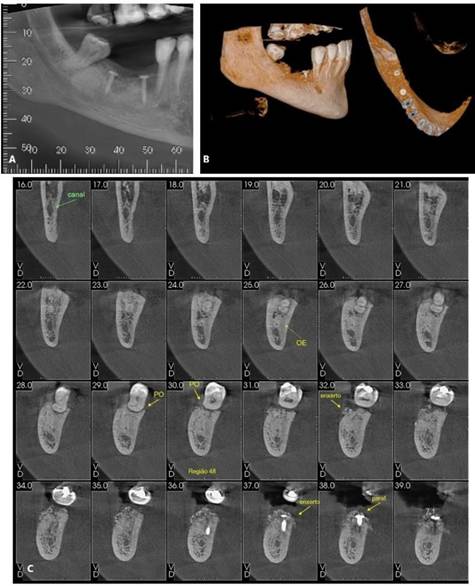

Paciente P. W. L, sexo masculino, 58 anos de idade, compareceu ao consultório particular para avaliação rotineira. O paciente relatou ausência de histórico de alterações sistêmicas e de alergias. Ao exame clínico e radiográfico, evidenciado comprometimento nos elementos 16 e 44. O tratamento consistiu inicialmente pela exodontia de ambos, preservação alveolar utilizando enxerto Cerabone (Straumann, Villeret, Suíça) e membrada de politetrafluoroetileno (PTFE). Após um período de 21 dias, a membrana foi removida. As figuras 26 (A -D), 27 (A – D) evidenciam o aspecto após as exodontias. Posteriormente, segui-se pela instalação de implante curto ARCSYS (FGM, Joinvile – SC, Brasil) 3,8mm x 7,0 mm na região do 16 e ARCSYS (FGM, Joinvile – SC, Brasil) 4,3 mm x 5,0 mm no 44. A reabilitação protética foi realizada através de próteses unitárias de cerâmica. O acompanhamento está sendo realizado até o presente momento, sem alterações significativas, com resultado clínico e radiográfico satisfatório (Figura 28. A – D).

Figura 26. A – D) TCFC das regiões edêntulas (16 e 44) após a exodontia de ambos.

Figura 27. A – E. Tomografia computadorixada de feixe curto (TCFC) evidenciada região edêntula do 44, após exodontia.

Figura 28. A – D) Resultado clínico e radiográfia após a reabilitação com implante e prótese no 44 e 16.